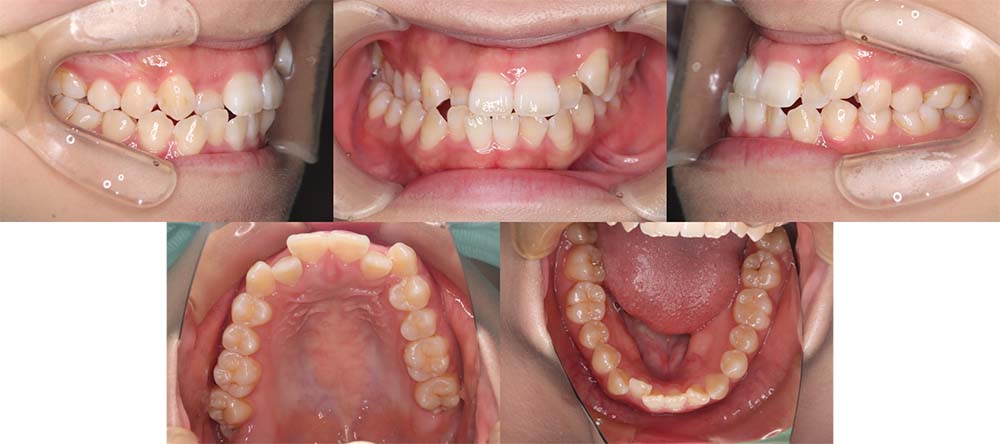

| 症例分類 | 顎変形症、叢生、側方偏移 |

| 診断名 | 下顎右側偏移を伴う上下叢生 |

| 主訴 | 歯並びがガタガタ、顎が右にずれている |

|---|---|

| 年齢 | 25歳4ヶ月 |

| 性別 | 女性 |

| 抜歯部位 | 上の左右第一小臼歯 |

| 使用装置 | 表側のワイヤー装置+外科矯正(手術を併用した治療) |

| 治療期間 | 2年1ヶ月 |

| 保定装置 | 固定式保定装置、取り外し式保定装置(8時間) |

| 費用 |

保険適応 [検査・診断等] 2万円程度 [装置装着] 5〜7万円程度 [調整料] 2,000〜7,000円程度/回 [手術前検査等] 2万円程度 [保定装置等] 4万円程度 合計18〜25万円程度 |

下顎の右側に偏移があり、骨格的にも受け口だったため、上顎両側第一小臼歯を抜去して、上下顎の手術を併用して治療を行いました。術前は前歯が反対のかみ合わせになり、初診時より咬合、顔貌は一旦悪くなります。術前矯正を1年7ヶ月した後に手術を行いました。

術後の顎間ゴムをしっかりと使用していただけたため、術後7ヶ月で治療が終了することができました。また、顎の歪みが残っていたため矯正治療終了後におとがい形成術をして、下顎の偏移を改善しました。

顎の歪みも下顎の前方感も改善することができ、上下のかみ合わせもしっかりと咬合することができました。